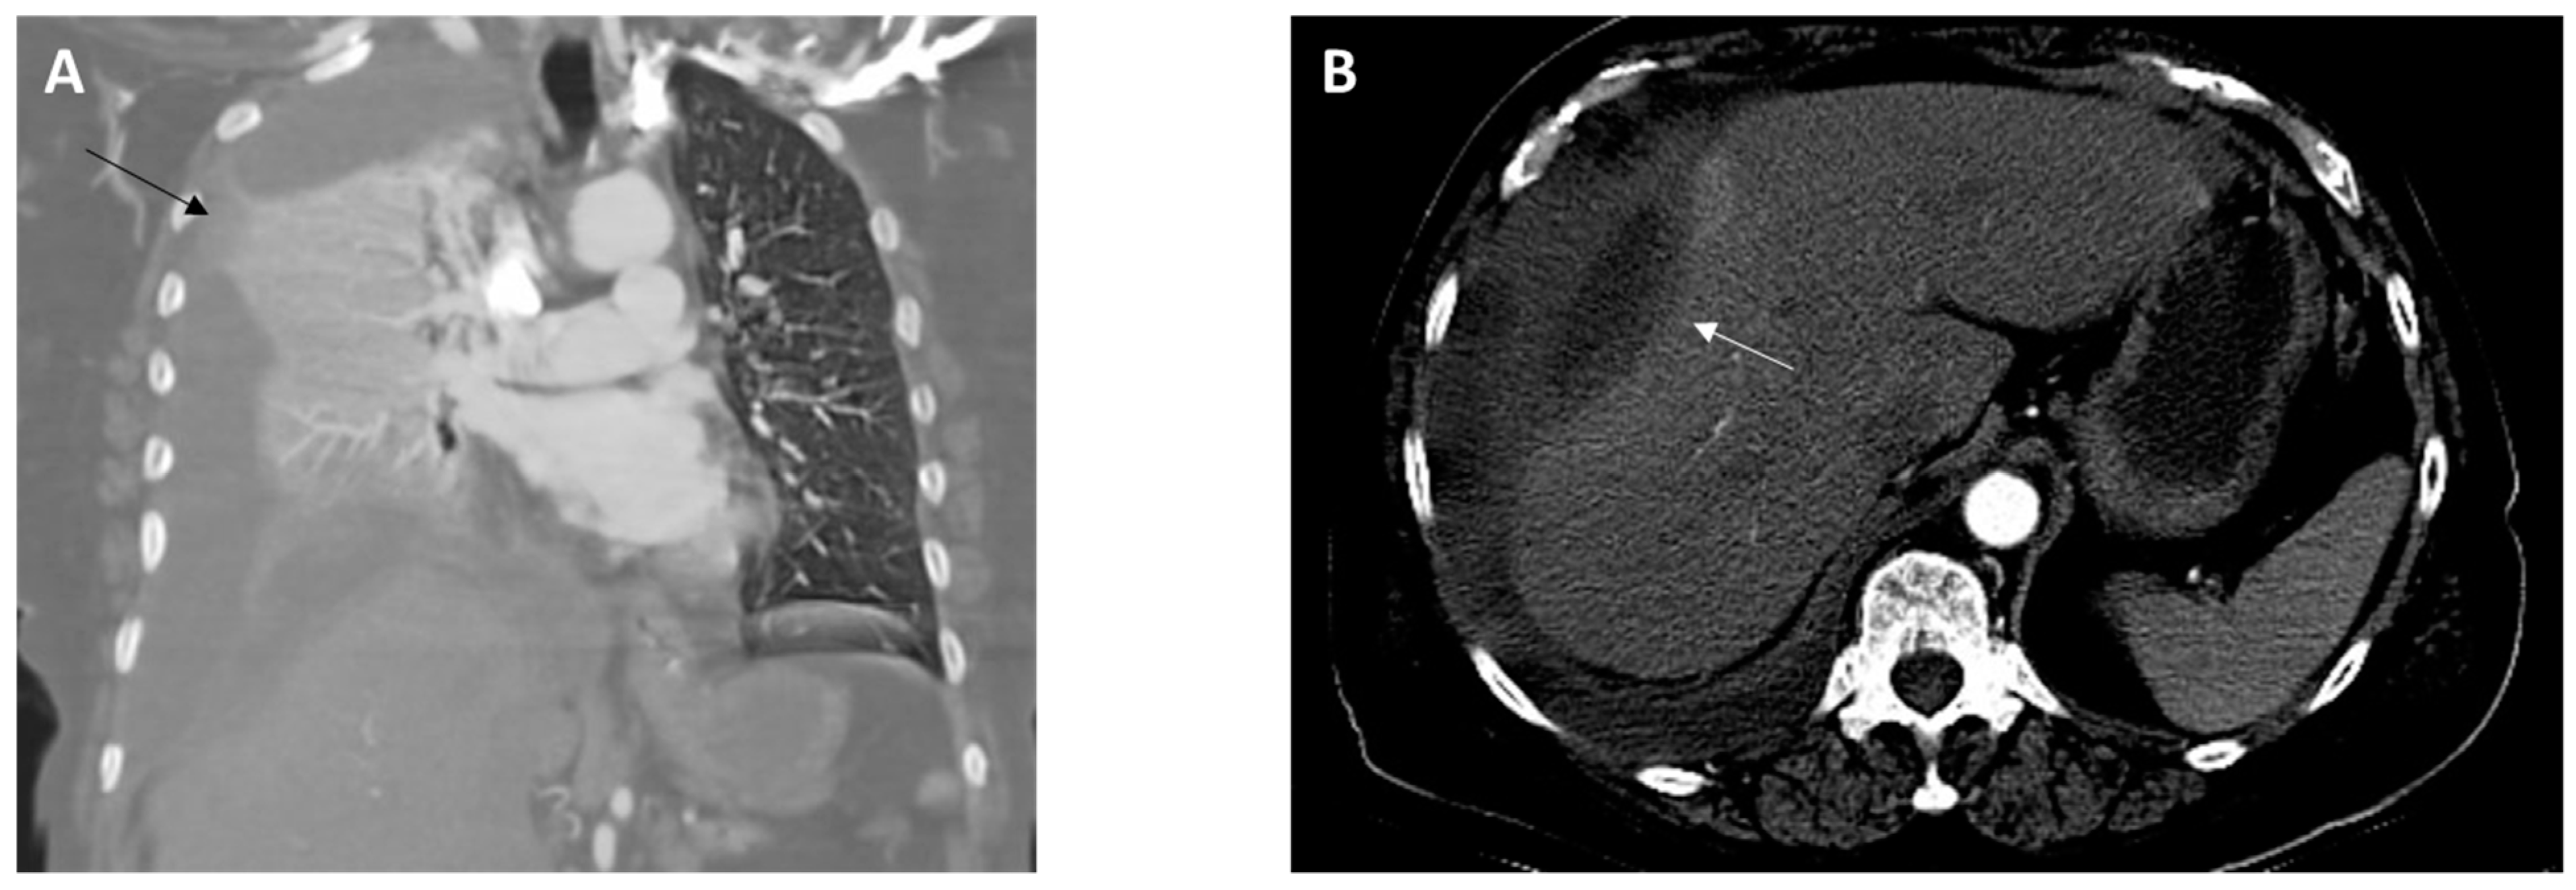

On arrival, she was found to be afebrile but tachycardic (116 beats per minute), tachypneic (26 breaths per minute), and hypoxic (SpO2 60–70% on room air). On physical examination, there was diminished air entry in the right lung and poor oral dentition, visualized with several loose or missing teeth along with visible tooth decay (dental caries). A complete blood count analysis revealed leukocytosis (25.57 k/µL; reference range, 4.50–11.00 k/uL). A comprehensive metabolic panel was unremarkable except for decreased carbon dioxide (14 mEq/L; reference range, 23–31 mEq/L). Elevated lactic acid (9.4 mmol/L; reference range, 0.5–2.0 mmol/L) and procalcitonin (10.05 ng/mL; reference range, 0.00–0.50 ng/mL) levels were detected. Chest X-ray imaging showed near-complete opacification of the right hemithorax. A computed tomography (CT) angiography of the chest revealed a large right hydropneumothorax with a leftward mediastinal shift (Figure 1A). The pleural fluid crossed the diaphragm, terminating in a thick-walled collection along the lateral aspect of the right lobe of the liver (Figure 1B). She developed progressive respiratory failure, requiring intubation and mechanical ventilation. The patient was administered intravenous (IV) vancomycin and piperacillin/tazobactam and was subsequently transferred to our facility for a thoracic surgery evaluation.

Figure 1.

Images from computed tomography angiography of the chest obtained at admission. (A), Coronal view revealing a collapsed right lung due to a large pleural effusion (black arrow). (B), Axial view showing the presence of a perihepatic abscess (10.0 × 3.8 cm) (white arrow).